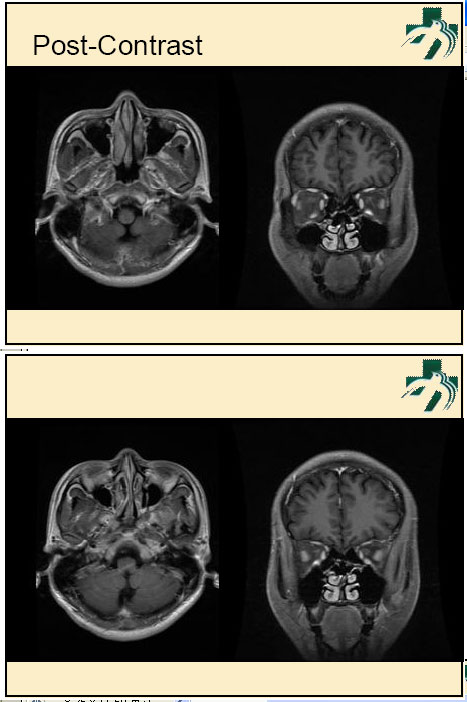

奴卡氏菌感染

第九期三博

读片会

病例之四

北京协和医院 提供

男性,22岁。自觉虫咬后皮疹、肢体麻木4月